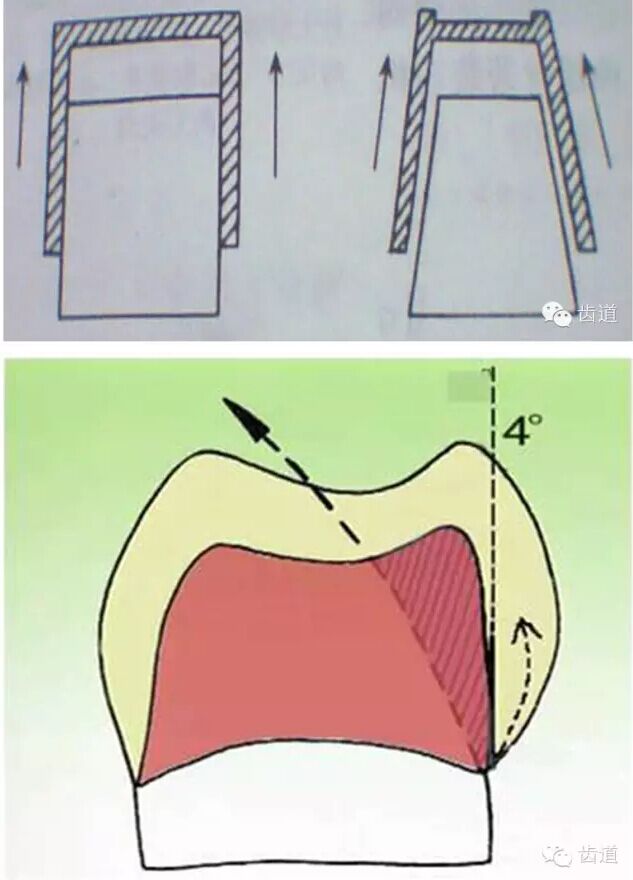

牙的外形及洞形的幾何形狀:主要是牙體制備出一定聚合角度產(chǎn)生的阻擋作用